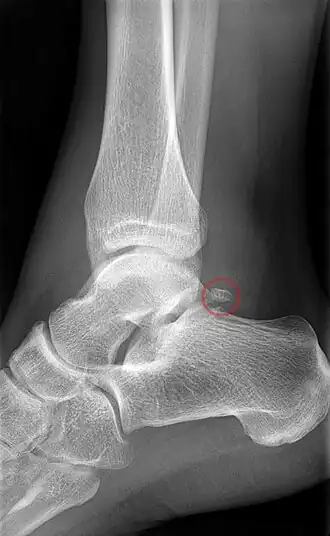

Os trigonum

Het os trigonum,[1] os intermedium tarsi,[1] os tali accessorium of os tali secundarium is een accessoir voetwortelbeentje dat zeer regelmatig als extra ossificatiepunt ontstaat gedurende de embryonale ontwikkeling.

Als het botje bij iemand voorkomt, is het gelegen aan de laterale tuberkel van de processus posterior van het sprongbeen.[2],[3] Het botje werd voor het eerst beschreven door de Duitse anatoom en chirurg Johann Christian Rosenmüller (1777-1820) in 1804.[4],[5] Het os trigonum is vaak gefuseerd of vormt een gewrichtsverbinding met het sprongbeen of het hielbeen.[2]

Het os trigonum is vaak een incidentele bevinding bij radiologisch onderzoek.[3] Op röntgenfoto's wordt het soms onterecht aangemerkt als afwijkend, losliggend botdeel of als fractuur.[9] Met name verwarring met een Shepherd-fractuur, een zeldzame fractuur van de laterale tuberkel van de processus posterior van het sprongbeen, komt veelvuldig voor.[2] Zelfs Shepherd maakte die vergissing.[10] In de verdere differentiaaldiagnose behoren een Cedell-fractuur (een fractuur van de mediale tuberkel van de processus posterior van de talus) en pseudartrose. Met behulp van CT en MRI kunnen ook het omliggende bot- en steunweefsel worden geëvalueerd om de klinische betekenis van het additionele botje vast te stellen.[3]